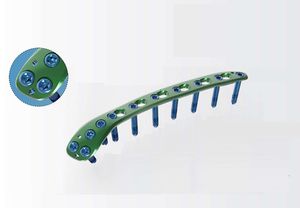

... ¢3.5/¢4.0 後壁臼蓋再建プレート 255.1141632.15 - ¢3.5/¢4.0 Posterior Acetabular-H Plate,16H L 255.2141632.15 - ¢3.5/¢4.0 Posterior Acetabular-H Plate,16H R 255.1140932.15 - ¢3.5/¢4.0 後壁臼蓋再建プレート,9H L 255.2140932.15 - ¢3.5/¢4.0 後壁臼蓋再建プレート,9H R 255.1141132.15 ...

Health-Joy Medical

... 255.1141632.15 - ¢3.5/¢4.0後側臼蓋-Hプレート 16H,L 255.2141632.15 - ¢3.5/¢4.0後側臼蓋-Hプレート16H、R ...

Health-Joy Medical

... 255.0150232.15 - ¢3.5/¢4.0寛骨臼スプリングフックプレート、ショート 255.0150332.15 - ¢3.5/¢4.0寛骨臼スプリングフック・プレート、ロング ...

Health-Joy Medical